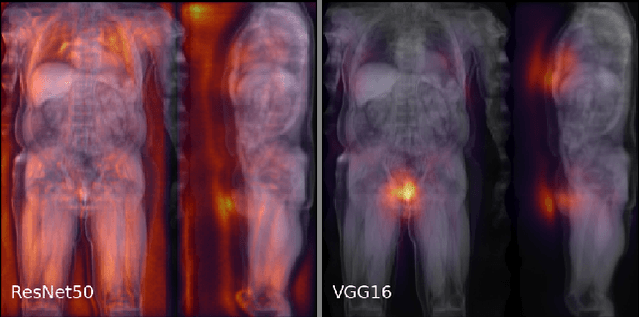

Abstract:Large-scale medical studies such as the UK Biobank examine thousands of volunteer participants with medical imaging techniques. Combined with the vast amount of collected metadata, anatomical information from these images has the potential for medical analyses at unprecedented scale. However, their evaluation often requires manual input and long processing times, limiting the amount of reference values for biomarkers and other measurements available for research. Recent approaches with convolutional neural networks for regression can perform these evaluations automatically. On magnetic resonance imaging (MRI) data of more than 40,000 UK Biobank subjects, these systems can estimate human age, body composition and more. This style of analysis is almost entirely data-driven and no manual intervention or guidance with manually segmented ground truth images is required. The networks often closely emulate the reference method that provided their training data and can reach levels of agreement comparable to the expected variability between established medical gold standard techniques. The risk of silent failure can be individually quantified by predictive uncertainty obtained from a mean-variance criterion and ensembling. Saliency analysis furthermore enables an interpretation of the underlying relevant image features and showed that the networks learned to correctly target specific organs, limbs, and regions of interest.

Abstract:Purpose: To enable fast and automated analysis of body composition from UK Biobank MRI with accurate estimates of individual measurement errors. Methods: In an ongoing large-scale imaging study the UK Biobank has acquired MRI of over 40,000 men and women aged 44-82. Phenotypes derived from these images, such as body composition, can reveal new links between genetics, cardiovascular disease, and metabolic conditions. In this retrospective study, neural networks were trained to provide six measurements of body composition from UK Biobank neck-to-knee body MRI. A ResNet50 architecture can automatically predict these values by image-based regression, but may also produce erroneous outliers. Predictive uncertainty, which could identify these failure cases, was therefore modeled with a mean-variance loss and ensembling. Its estimates of individual prediction errors were evaluated in cross-validation on over 8,000 subjects, tested on another 1,000 cases, and finally applied for inference. Results: Relative measurement errors below 5\% were achieved on all but one target, for intra-class correlation coefficients (ICC) above 0.97 both in validation and testing. Both mean-variance loss and ensembling yielded improvements and provided uncertainty estimates that highlighted some of the worst outlier predictions. Combined, they reached the highest quality, but also exhibited a consistent bias towards high uncertainty in heavyweight subjects. Conclusion: Mean-variance regression and ensembling provided complementary benefits for automated body composition measurements from UK Biobank MRI, reaching high speed and accuracy. These values were inferred for the entire cohort, with uncertainty estimates that can approximate the measurement errors and identify some of the worst outliers automatically.

Abstract:The UK Biobank Imaging Study has acquired medical scans of more than 40,000 volunteer participants. The resulting wealth of anatomical information has been made available for research, together with extensive metadata including measurements of liver fat. These values play an important role in metabolic disease, but are only available for a minority of imaged subjects as their collection requires the careful work of image analysts on dedicated liver MRI. Another UK Biobank protocol is neck-to-knee body MRI for analysis of body composition. The resulting volumes can also quantify fat fractions, even though they were reconstructed with a two- instead of a three-point Dixon technique. In this work, a novel framework for automated inference of liver fat from UK Biobank neck-to-knee body MRI is proposed. A ResNet50 was trained for regression on two-dimensional slices from these scans and the reference values as target, without any need for ground truth segmentations. Once trained, it performs fast, objective, and fully automated predictions that require no manual intervention. On the given data, it closely emulates the reference method, reaching a level of agreement comparable to different gold standard techniques. The network learned to rectify non-linearities in the fat fraction values and identified several outliers in the reference. It outperformed a multi-atlas segmentation baseline and inferred new estimates for all imaged subjects lacking reference values, expanding the total number of liver fat measurements by factor six.